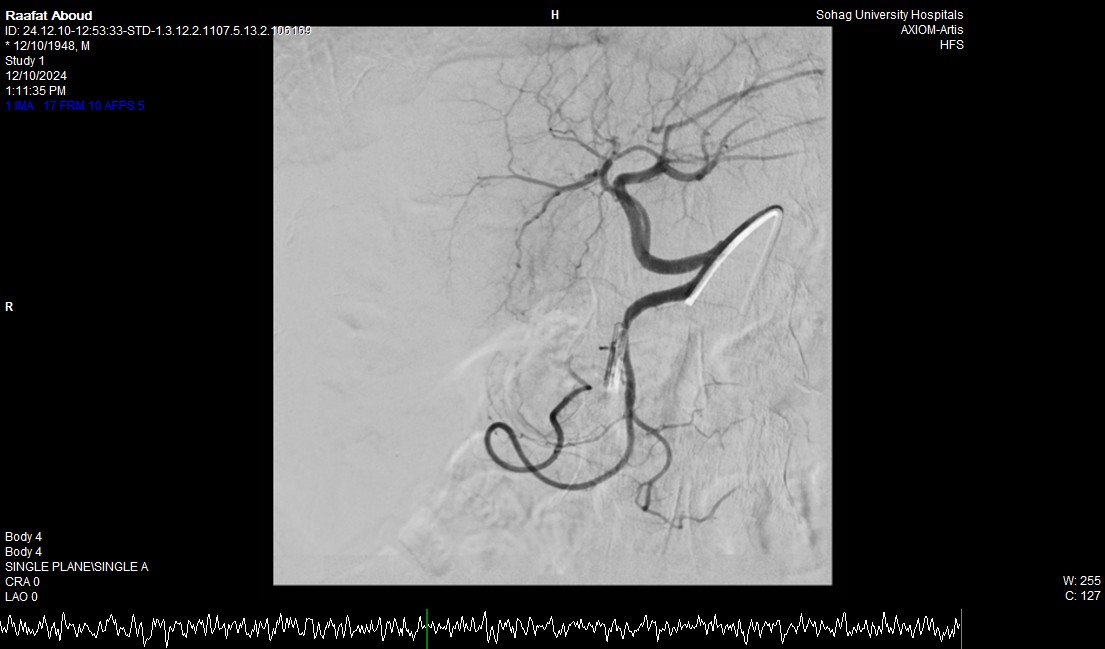

جامعة سوهاج.. أفاد الدكتور أحمد كمال، المدير التنفيذي للمستشفيات الجامعية، أن الفحوصات أظهرت وجود قرحة كبيرة في الاثني عشر وشريان نازف. نجح الفريق الطبي في التحكم بالنزيف مبدئيًا عبر تركيب مشبك معدني بالمنظار وحقن القرحة النازفة.

جامعة سوهاج.. وفي خطوة لاحقة، تم استدعاء فريق الأشعة التداخلية الذي تمكن من إغلاق الشريان النازف بشكل عاجل باستخدام جهاز القسطرة، ما ساهم في استقرار حالة المريض.

جامعة سوهاج.. أكد الدكتور محمد زاكي، رئيس قسم الأشعة، أن مثل هذه الحالات تعد من أخطر الطوارئ الطبية، حيث يتطلب التعامل معها إجراء قسطرة شريانية عاجلة لإيقاف النزيف. وأضاف أن وحدة الأشعة التداخلية مزودة بجهاز أشعة محوري متقدم مخصص لمثل هذه التدخلات، مشيرًا إلى أن هذا النجاح يعكس التعاون المثمر بين أقسام المستشفى المختلفة ووحدة الأشعة التداخلية لتقديم خدمات متميزة للمرضى.